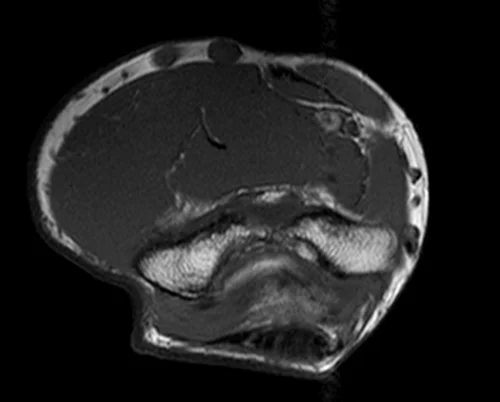

mri elbow axial t1 image 1 - MRI